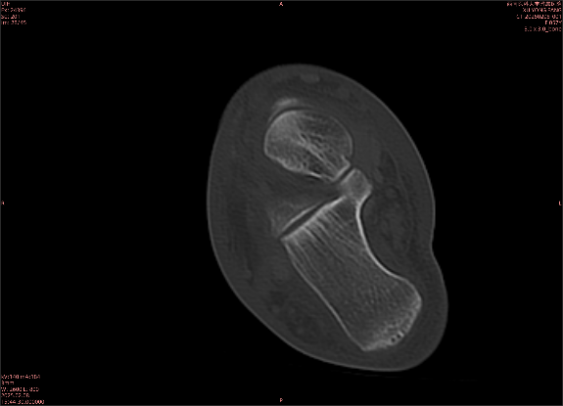

舉例圖像

圖1

專業(yè)解釋看不懂沒關(guān)系,大家看圖1和圖2就可以了,這是同一個(gè)患者跟骨的磁共振和CT圖像,圖1的紅色箭頭指示的黑線就是磁共振圖像顯示的骨折線,一目了然。而對比圖2的CT圖像上并未顯示異常。

這下大家明白了吧,如果懷疑隱匿性骨折優(yōu)先選擇磁共振檢查